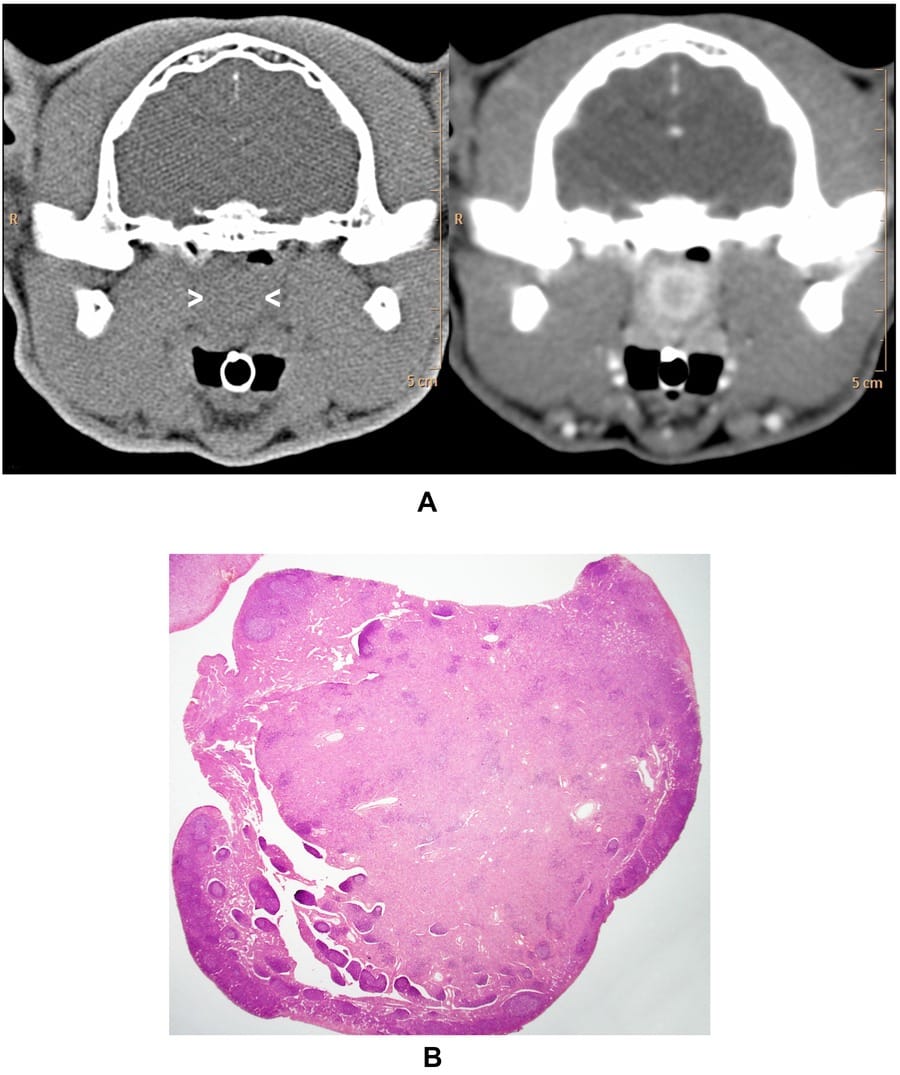

Example of an inflamed nasopharyngeal polyp in a 14-year-old domestic short haired cat. (A) The polyp (arrowheads) has moderate attenuation (40 HU) in precontrast CT image (at left) and is difficult to distinguish from the surrounding tissues. In postcontrast CT image (at right), the polyp has a relatively marked increase in attenuation of the core (120 HU) and rim (191 HU). The rim appears complete in this image. A slight amount of noncontrast-enhancing material, probably exudate, separates the polyp from adjacent nasopharyngeal mucosa. (B) Corresponding histologic section of the polyp (maximal diameter 10 mm), which was graded as having moderate edema and inflammatory infiltrate in the core stroma and marked inflammatory infiltrate in the peripheral stroma (note deep staining; H&E stain).